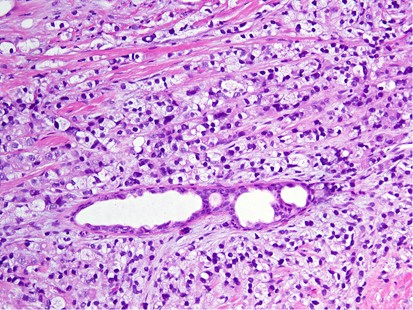

Glass slides were available for review in 53 out of 85 (62%) cases. These slides included 28 core biopsies and 30 excisions (5 cases with both cores and excisions). Seven cases involved lymph nodes only (6 axillary and 1 intramammary). The remaining 46 cases all involved the breast. Mammary lymphatic only involvement, without stromal invasion, occurred in 7% (3/46) of the cases. Certain recurrent histological features were identified, including a well-circumscribed nodule (74%, 34/46), often surrounded by a fibrous pseudocapsule (52%, 24/46) with varying thickness (Figure 1) and absence of an in situ mammary carcinoma. Interestingly, in the great majority of the tumors, lymphovascular invasion was notably absent (87%, 40/46). Tumoral calcifications were observed in non-mammary metastases of serous carcinoma type that were psammomatous in nature (75%, 6/8) (Figure 2), including two cases that involved lymph nodes.

High-grade ovarian serous carcinoma metastatic to the breast. The tumor has overlapping morphologic features with primary breast cancer with medullary or atypical medullary features including a solid growth pattern, central necrosis, a host inflammatory response and marked cytologic atypia. Ovarian high-grade serous carcinoma was the most commonly misdiagnosed tumor in this series.